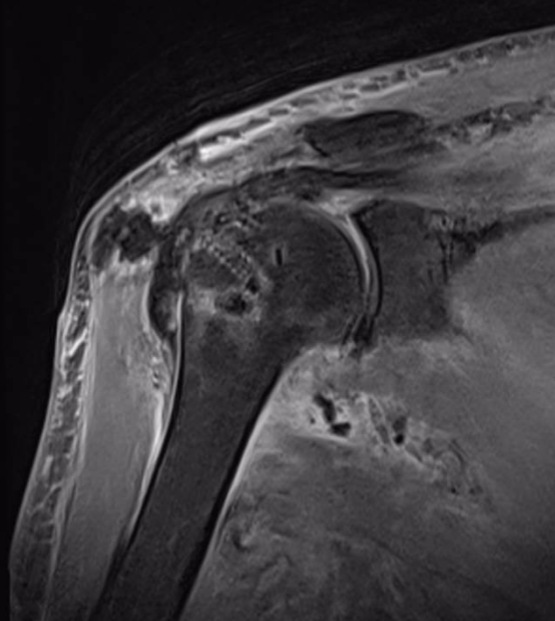

患者党某,1 年前无明显诱因出现右肩关节疼痛,尤其肩关节上举外展疼痛剧烈,右手不能搭到左肩上,近日疼痛逐渐加重生活受到严重影响,遂来延安市中医医院运动医学科求诊。

北京大学第三医院驻延专家林霖教授、运动医学科主任庞军、副主任张志宇、刘博旭医师团队综合评估了患者病情,尊重患者及家属意愿,为患者制定了周密的微创手术治疗方案。

由于巨大肩袖撕裂手术难度大, 对缝合及重建的技术要求高,需要扎实的手术经验及操作技术才能完成。手术中手术团队默契配合,在关节镜下经充分松解后行肩袖修补,手术顺利完成,患者现恢复情况良好。